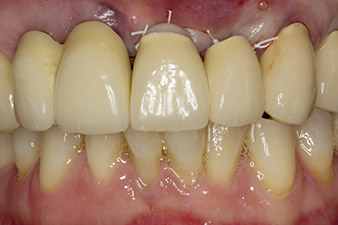

Alla prima visita, il paziente si presentava con ricostruzione su denti 21, 22 e 23 eseguita mediante corone splintate, ormai 19 anni prima, fissate agli impianti con attacchi in corrispondenza delle posizioni 12/11 (cfr. Fig. 2).

L'esito radiologico ha rivelato perdita di tessuto osseo in orizzontale attorno ai denti 21 e 22 (Fig. 1). Quando si è passati a rimuovere la corona, questi stessi denti sono stati estratti involontariamente.

Il dente 23 mostrava una frattura coronale orizzontale ricostruita mediante procedura post-endodontica con posizionamento di moncone core protesico temporaneo. Si è previsto di posizionare un ponte in ossido di zirconio sugli impianti esistenti in corrispondenza delle posizioni 12 e 11 e di posizionare due nuovi impianti in corrispondenza delle posizioni 22 e 23.